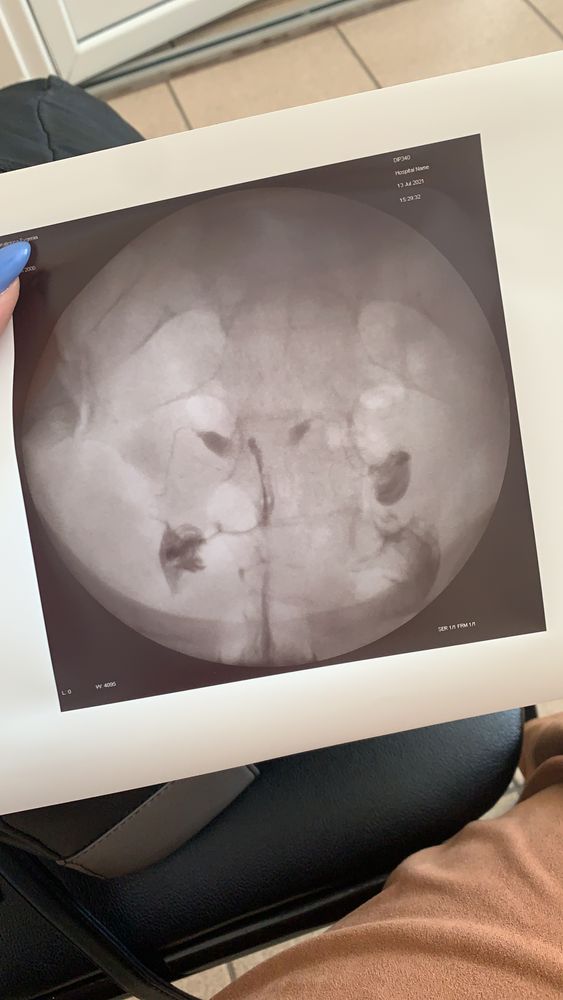

Помогите расшифровать результаты ГСГ!)

Сделали ГСГ , доктор делавшая его сказала все нормально. Мой лечащий доктор сказала , что ей не нравится результат, плохопроходимы трубы , левая труба вообще под вопросом и даёт направление на лапароскопияю. Но вроде на снимке жидкость вышла , следовательно они проходимы , или нет?! Помогите разобраться , кто сталкивался!)

У меня по гсг показало что одна труба не проходима, отправили на лапару, оказалось все проходимо